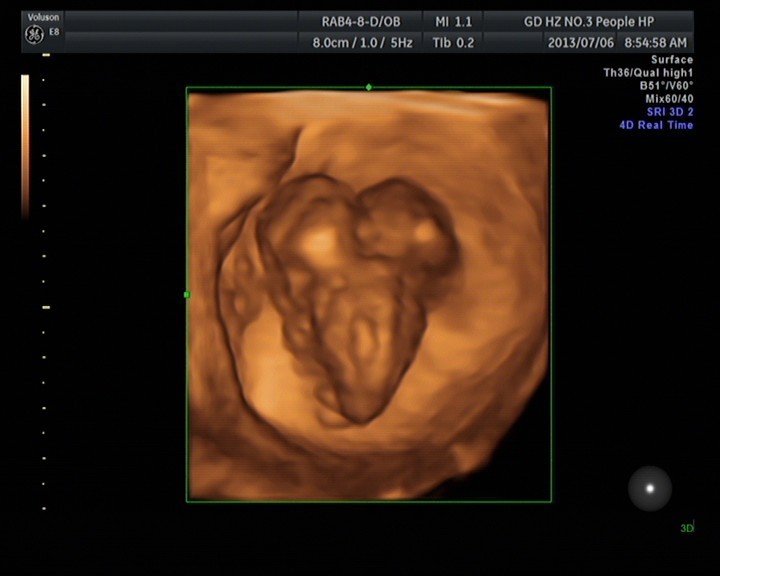

隨著環(huán)境污染日益嚴重,隨著各種地溝油的誕生,隨著各樣鎘大米的泛濫……我們的健康越來越受到威脅,很多疾病也隨之接踵而至,胎兒先天性疾病也越來越多見。7月6日,我院超聲科王瑤醫(yī)生在做胎兒產(chǎn)前NT篩查中發(fā)現(xiàn)一例孕約11周+的聯(lián)體雙胎。超聲所見:增大的子宮內(nèi)可見聯(lián)體雙胎兒回聲,可見兩個胎頭不能分離,胸部及腹部融合,可見一個增大的心臟。

聯(lián)體嬰兒B超圖像